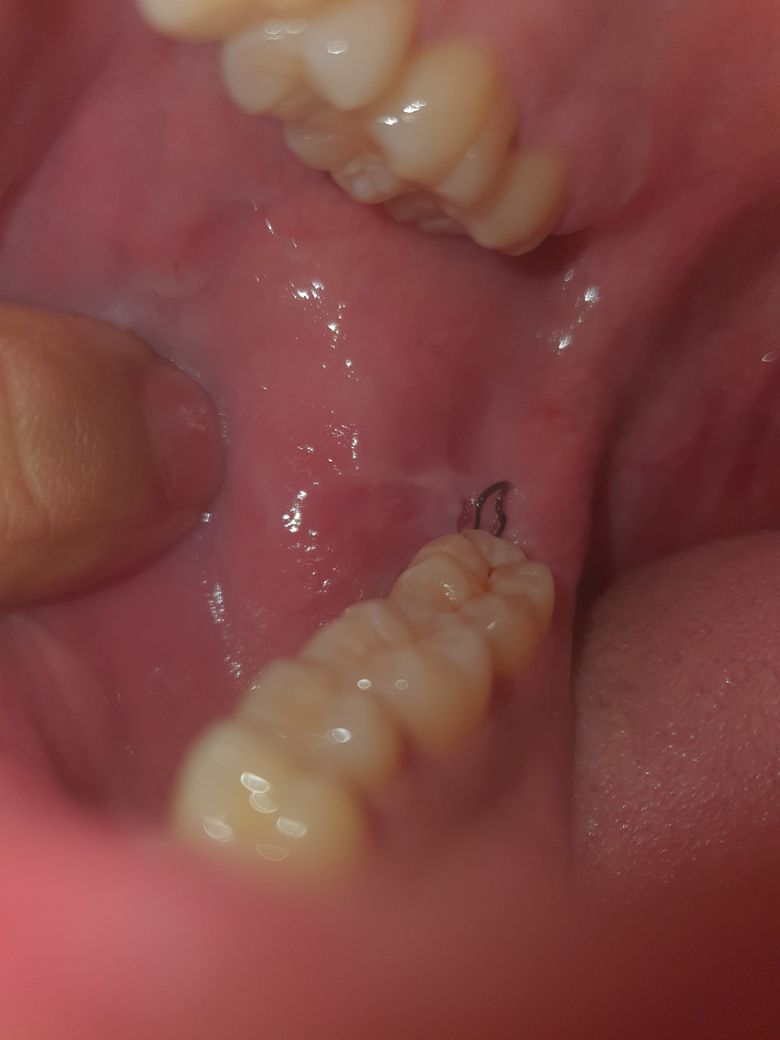

매복사랑니 발치 후 이거 실밥 터진건가요?

이번주 월요일(5일)에 발치했고 사진은 오늘입니다

뭔가 갈라진게 확인이 되고

사랑니 발치 이후에 실밥은 자주 풀리게 되며 큰 문제를 일으키지 않습니다. 현재 사진 상으로 보아서 전혀 이상이 없고 정상적인 회복 과정으로 보입니다. 지금 시기에는 피떡이 보이지 않는 것이 맞으며 특별한 통증이 없고 모양이 이상하지 않기 때문에 별다른 문제는 없을 것으로 보입니다. 걱정하지 않으셔도 됩니다.

사진상으로 크게 문제가 되보이진 않습니다. 지혈이 잘되셧으면 문제없으니 약속날짜에 가시면될것같습니다.

정상적으로 치유가 되고 있는 것으로 보이며 특별히 이상이 보이지는 않습니다.

발치 부위가 부었다 가라앉으면서 실밥이 느슨해 질수있고 혈병이 없이 잘 아무는 경우도 있습니다.